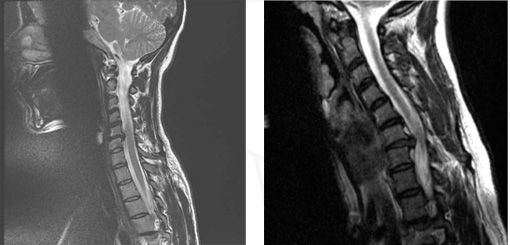

Des cas cliniques documentés relatent des blessures cervicales (lésions et complications vasculaires) liées à la pratique de Halasana et Salamba Sarvangasana. Même chez des pratiquants avancés, la zone du rachis cervical peut être fortement impactée, ce que confirment des imageries médicales.